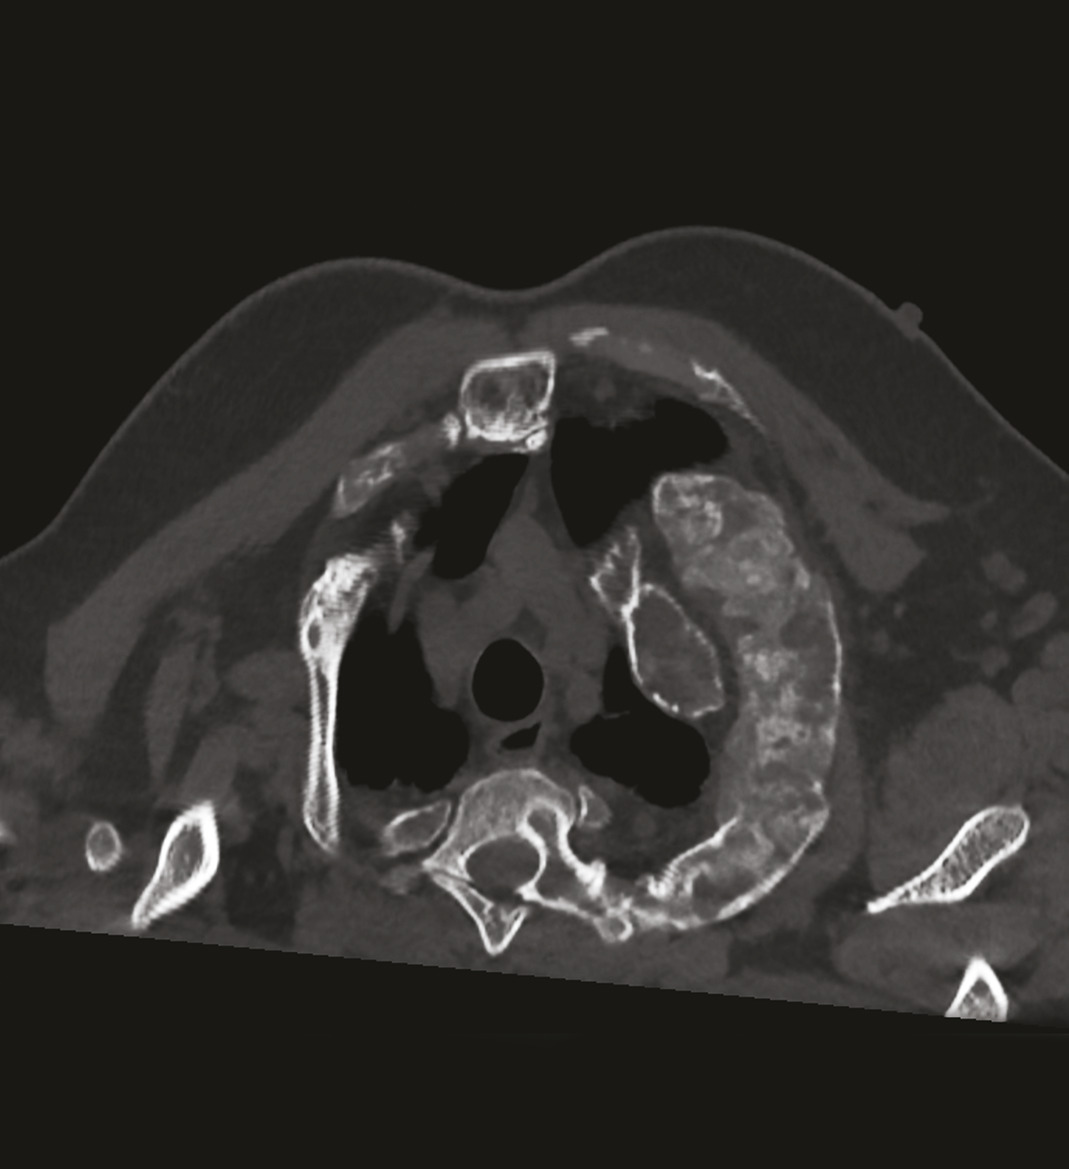

Les images de scanner (fig. 3-5) mettent en évidence de multiples lésions soufflantes avec un aspect en verre dépoli de l’os trabéculaire refoulant la corticale ainsi qu’une érosion marquée de la corticale, sans réaction périostée, confirmant une dysplasie fibreuse polyostotique prédominant au niveau des côtes et du rachis, sans sténose canalaire.